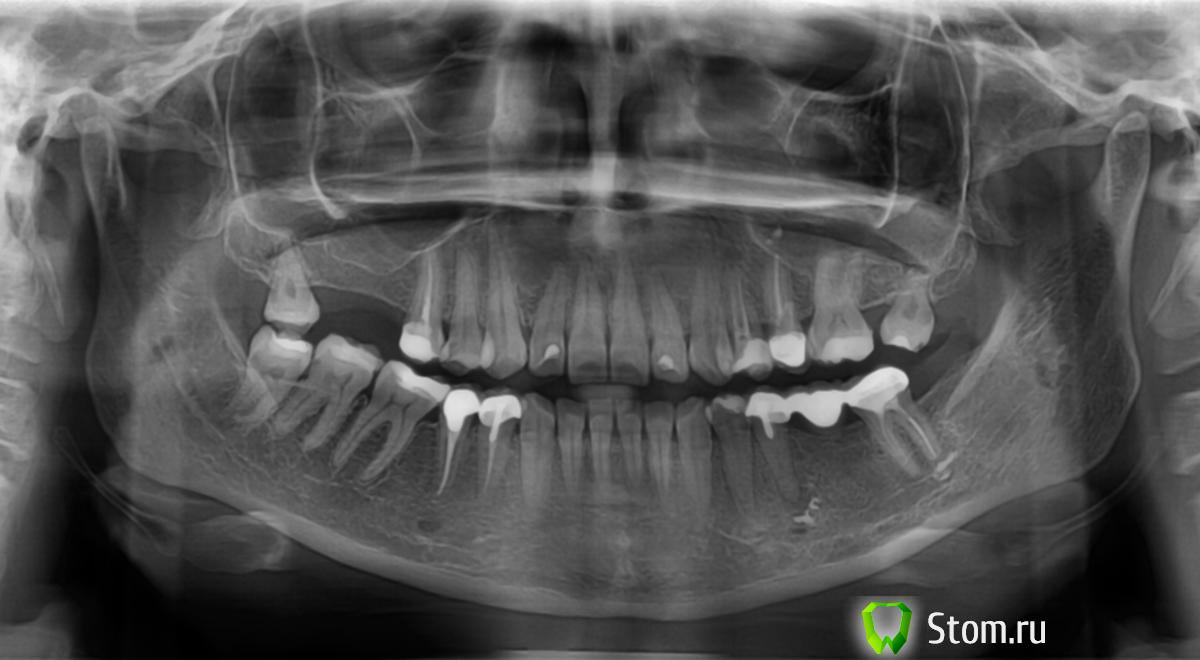

umka-izh Опубликовано 10 декабря, 2011 Поделиться Опубликовано 10 декабря, 2011 Полгода назад появилась небольшая припухлость, сейчас она увеличилась. Какие варианты лечения могут предложить? Снимок прилагаю. Ссылка на комментарий

Afffinity Опубликовано 10 декабря, 2011 Поделиться Опубликовано 10 декабря, 2011 Cнять мост, извлечь вкладку и для начала пролечить канал Ссылка на комментарий

umka-izh Опубликовано 11 декабря, 2011 Автор Поделиться Опубликовано 11 декабря, 2011 Там где стоит мост. Ссылка на комментарий

umka-izh Опубликовано 11 декабря, 2011 Автор Поделиться Опубликовано 11 декабря, 2011 Мостовой протез был поставлен меньше года назад, и если его снимать и пролечивать, то придется заново ставить? Такой случай входит в гарантию, которую дают при установке коронок? Ссылка на комментарий